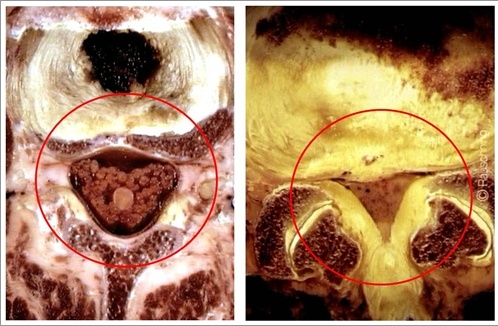

2.CT检查 应用CT检查脊椎与椎管内病变在临床上已广泛开展,分辨率相对为高的CT图像,可较清楚地显示椎间盘突出的部位、大小、形态和神经根、硬脊膜囊受压移位的形象,同时可显示椎板及黄韧带肥厚、小关节增生肥大、椎管及侧隐窝狭窄等情况,并可以三维技术重建椎管与根管的立体形态。从影像学角度来看,本病在CT图像上的主要改变有以下几点(图6):

(1)椎间盘后缘变形:正常情况下,椎间盘后缘与椎体骨性断面的边缘平行;在髓核突出的患者,椎间盘后缘有一局部突出。根据局部改变的形态与性质,可区分椎间盘膨出、突出或脱出(破裂),前者为退行性变的早期表现,后两者则属中、后期改变。

(2)硬膜外脂肪消失:正常情况下,腰椎区域,尤其是腰4~5和腰5~骶1平面,硬脊膜囊通常有丰富的硬膜外脂肪,硬膜外透亮区的形态和大小对称。当椎间盘破裂时,脱出的髓核可以替代低密度的硬膜外脂肪,在椎间盘破裂的平面上,两侧对比观察,密度并不对称。

(3)硬膜外间隙中的软组织密度增高:突出或脱出髓核的密度高于硬脊膜囊和硬膜外脂肪,硬膜外间隙中的软组织密度阴影代表突出的碎片(大小和位置)。当碎片较小而外面有后纵韧带连着时,其软组织块影与椎间盘影相连续。当碎片已破裂到后纵韧带外面,且与椎间盘失去连续性和从纤维环破裂处游离时,可出现分离状影像。根据椎间盘破裂的部位,软组织密度可能位于中线或后外侧缘,若破裂完全发生在外侧缘,则软组织密度位于椎间孔内。当突出的碎片较大时,在病变椎间盘平面以外的层面上也可显示软组织密度。根据碎片游离方向,可能位于椎间盘下方的椎体后缘,或紧靠椎弓根的侧隐窝内;亦可能位于椎孔内,颇像增大的神经节。

(4)硬脊膜囊变形:硬脊膜及其内容物的密度低于椎间盘。在上部腰椎区域,整个骨性椎管全部由脊膜囊占据。脊膜囊缘和椎间盘边缘之间由于密度差的关系,分界清楚。当椎间盘突出时,硬脊膜囊也可变形。在下部腰椎区域,硬脊膜囊并不充盈整个骨性椎管,也不与椎间盘后缘接触,仅当椎间盘突出相当大,足以将硬膜外脂肪堵塞并压迫脊膜囊壁时,光滑圆形的脊膜囊轮廓才出现变形,突出的碎片可能压迫神经根;亦有少数病例并不引起脊膜囊变形。

(5)神经根鞘的受压移位:在正常情况下,神经根鞘在硬膜外脂肪对比下表现为软组织密度,其位于骨性椎管的后侧、椎弓根的内侧,在椎弓根稍下方的平面上,当碎片向骨性椎管后侧突出时,将根鞘向后推移,根鞘与突出的碎片常无法区分,这本身就是神经根受压的一种征象。

(6)突(脱)出髓核的钙化:髓核突(脱)出时间较久者,可逐渐形成钙化,并在CT检查中出现相一致的改变。碎片与椎间隙边缘可以相延缓。

(7)CTM检查技术:CT检查技术对椎间盘突出的诊断准确率为80%~92%。由于CT检查对患者的X线照射量小,可列为基本无害的诊断手段。此外,用水溶性造影剂做脊髓造影与CT检查结合(CTM),能提高诊断的准确性。在CTM检查时,上述征象更为明显。在大多数椎间盘突出症患者,受椎间盘压迫的神经根和硬膜囊在同一平面。游离型椎间盘脱出则可发生于椎管内的其他部位。